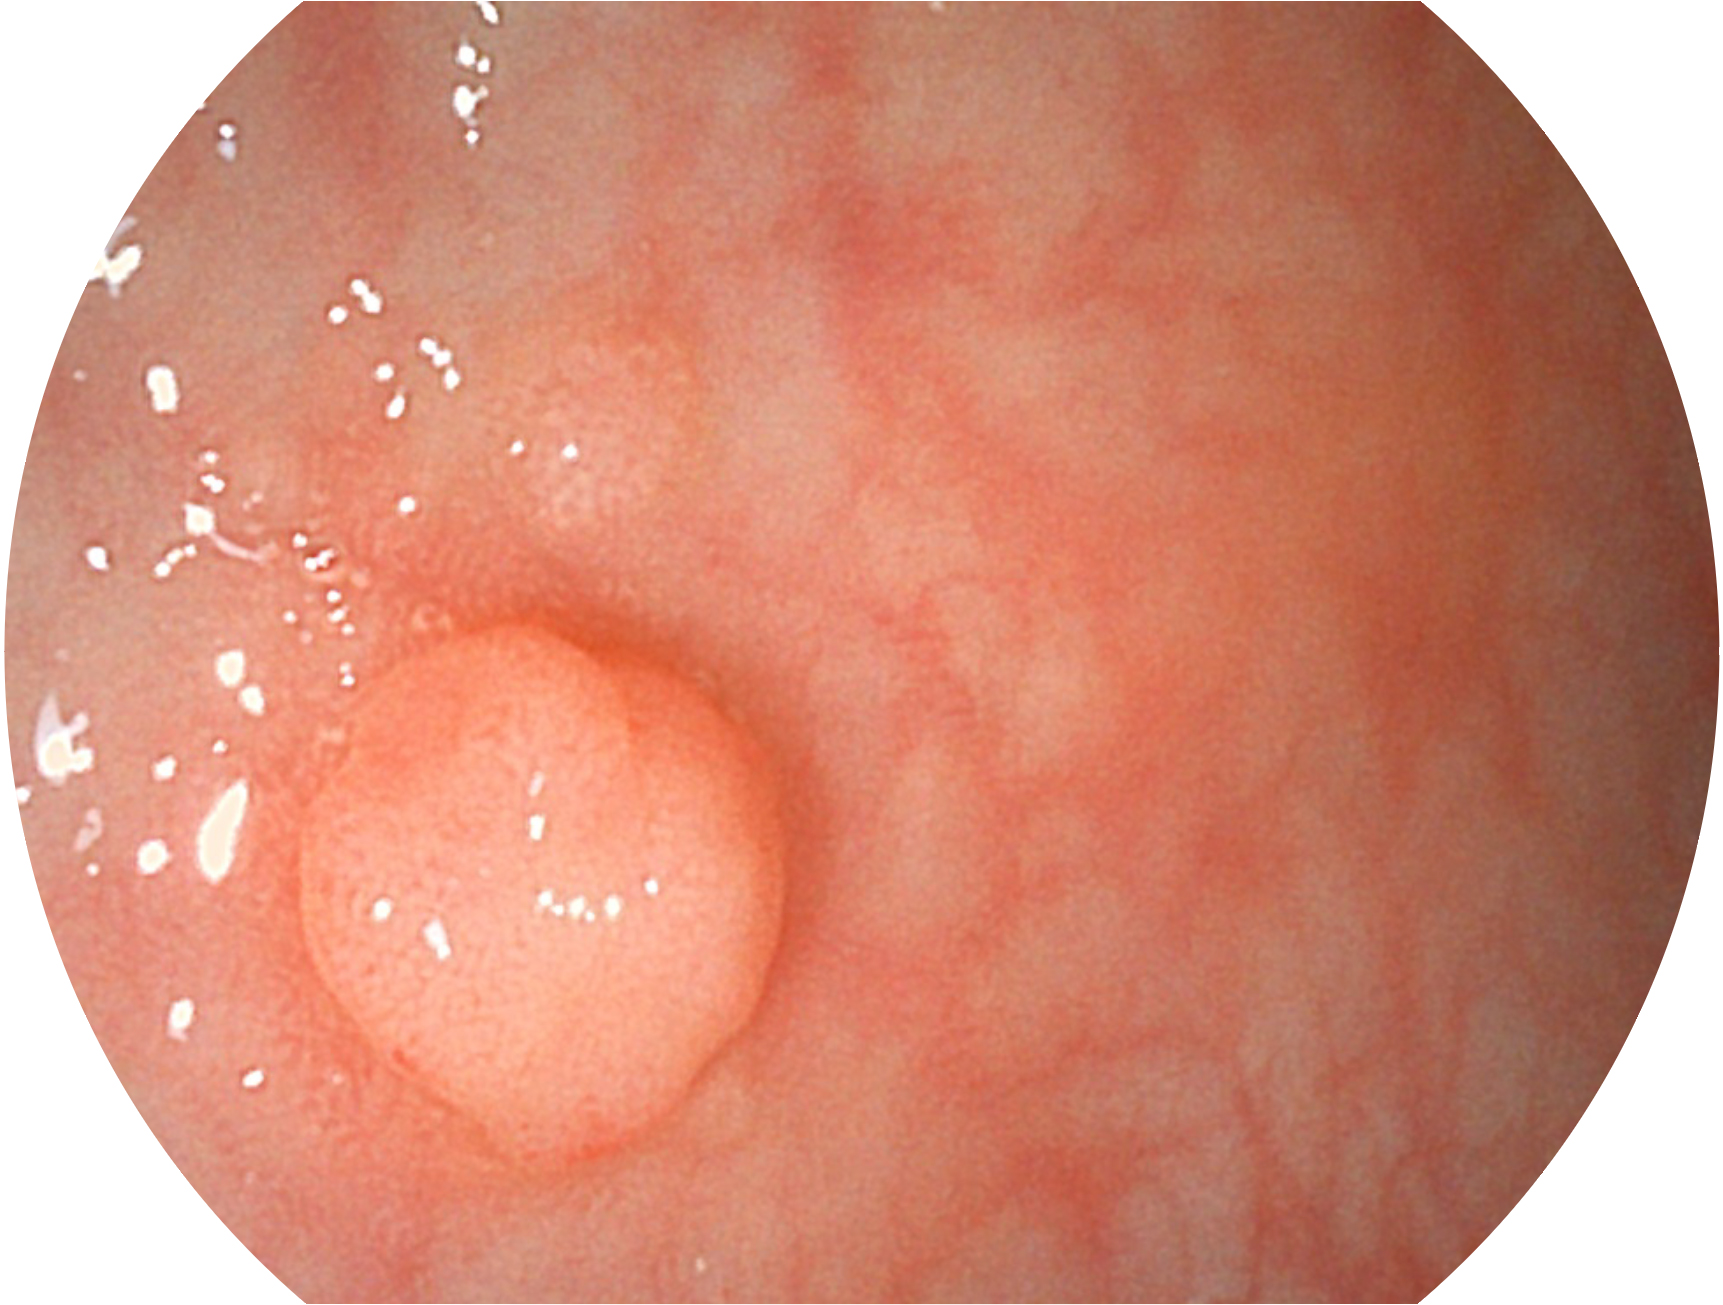

• 白光图像 SFI图像